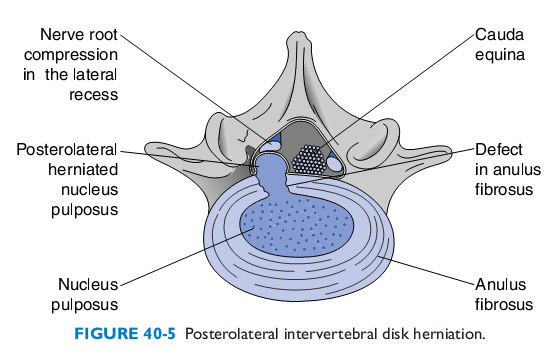

Thoát vị đĩa đệm là tình trạng nhân nhầy đĩa đệm cột sống thoát ra khỏi vị trí bình thường trong vòng sợi chèn ép vào ống sống hay các rễ thần kinh sống.

Hình 1: Thoát vị đĩa đệm sau bên

- Loại thoát vị cạnh trung tâm (sau-bên, posterial-lateral) chèn ép cả tủy và rễ thần kinh gây ra bệnh lý tủy rễ.

- Loại thoát vị cạnh bên (xa bên, far-lateral) còn gọi là thoát vị lỗ ghép chủ yếu chèn ép rễ thần kinh gây ra bệnh lý rễ.